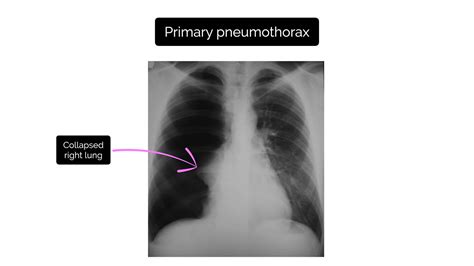

Simple Pneumothorax

A simple pneumothorax is the most common type and occurs when air enters the pleural space without any underlying lung disease. On an X-ray, it appears as a thin line separating the lung from the chest wall, with no visible lung markings beyond this line.